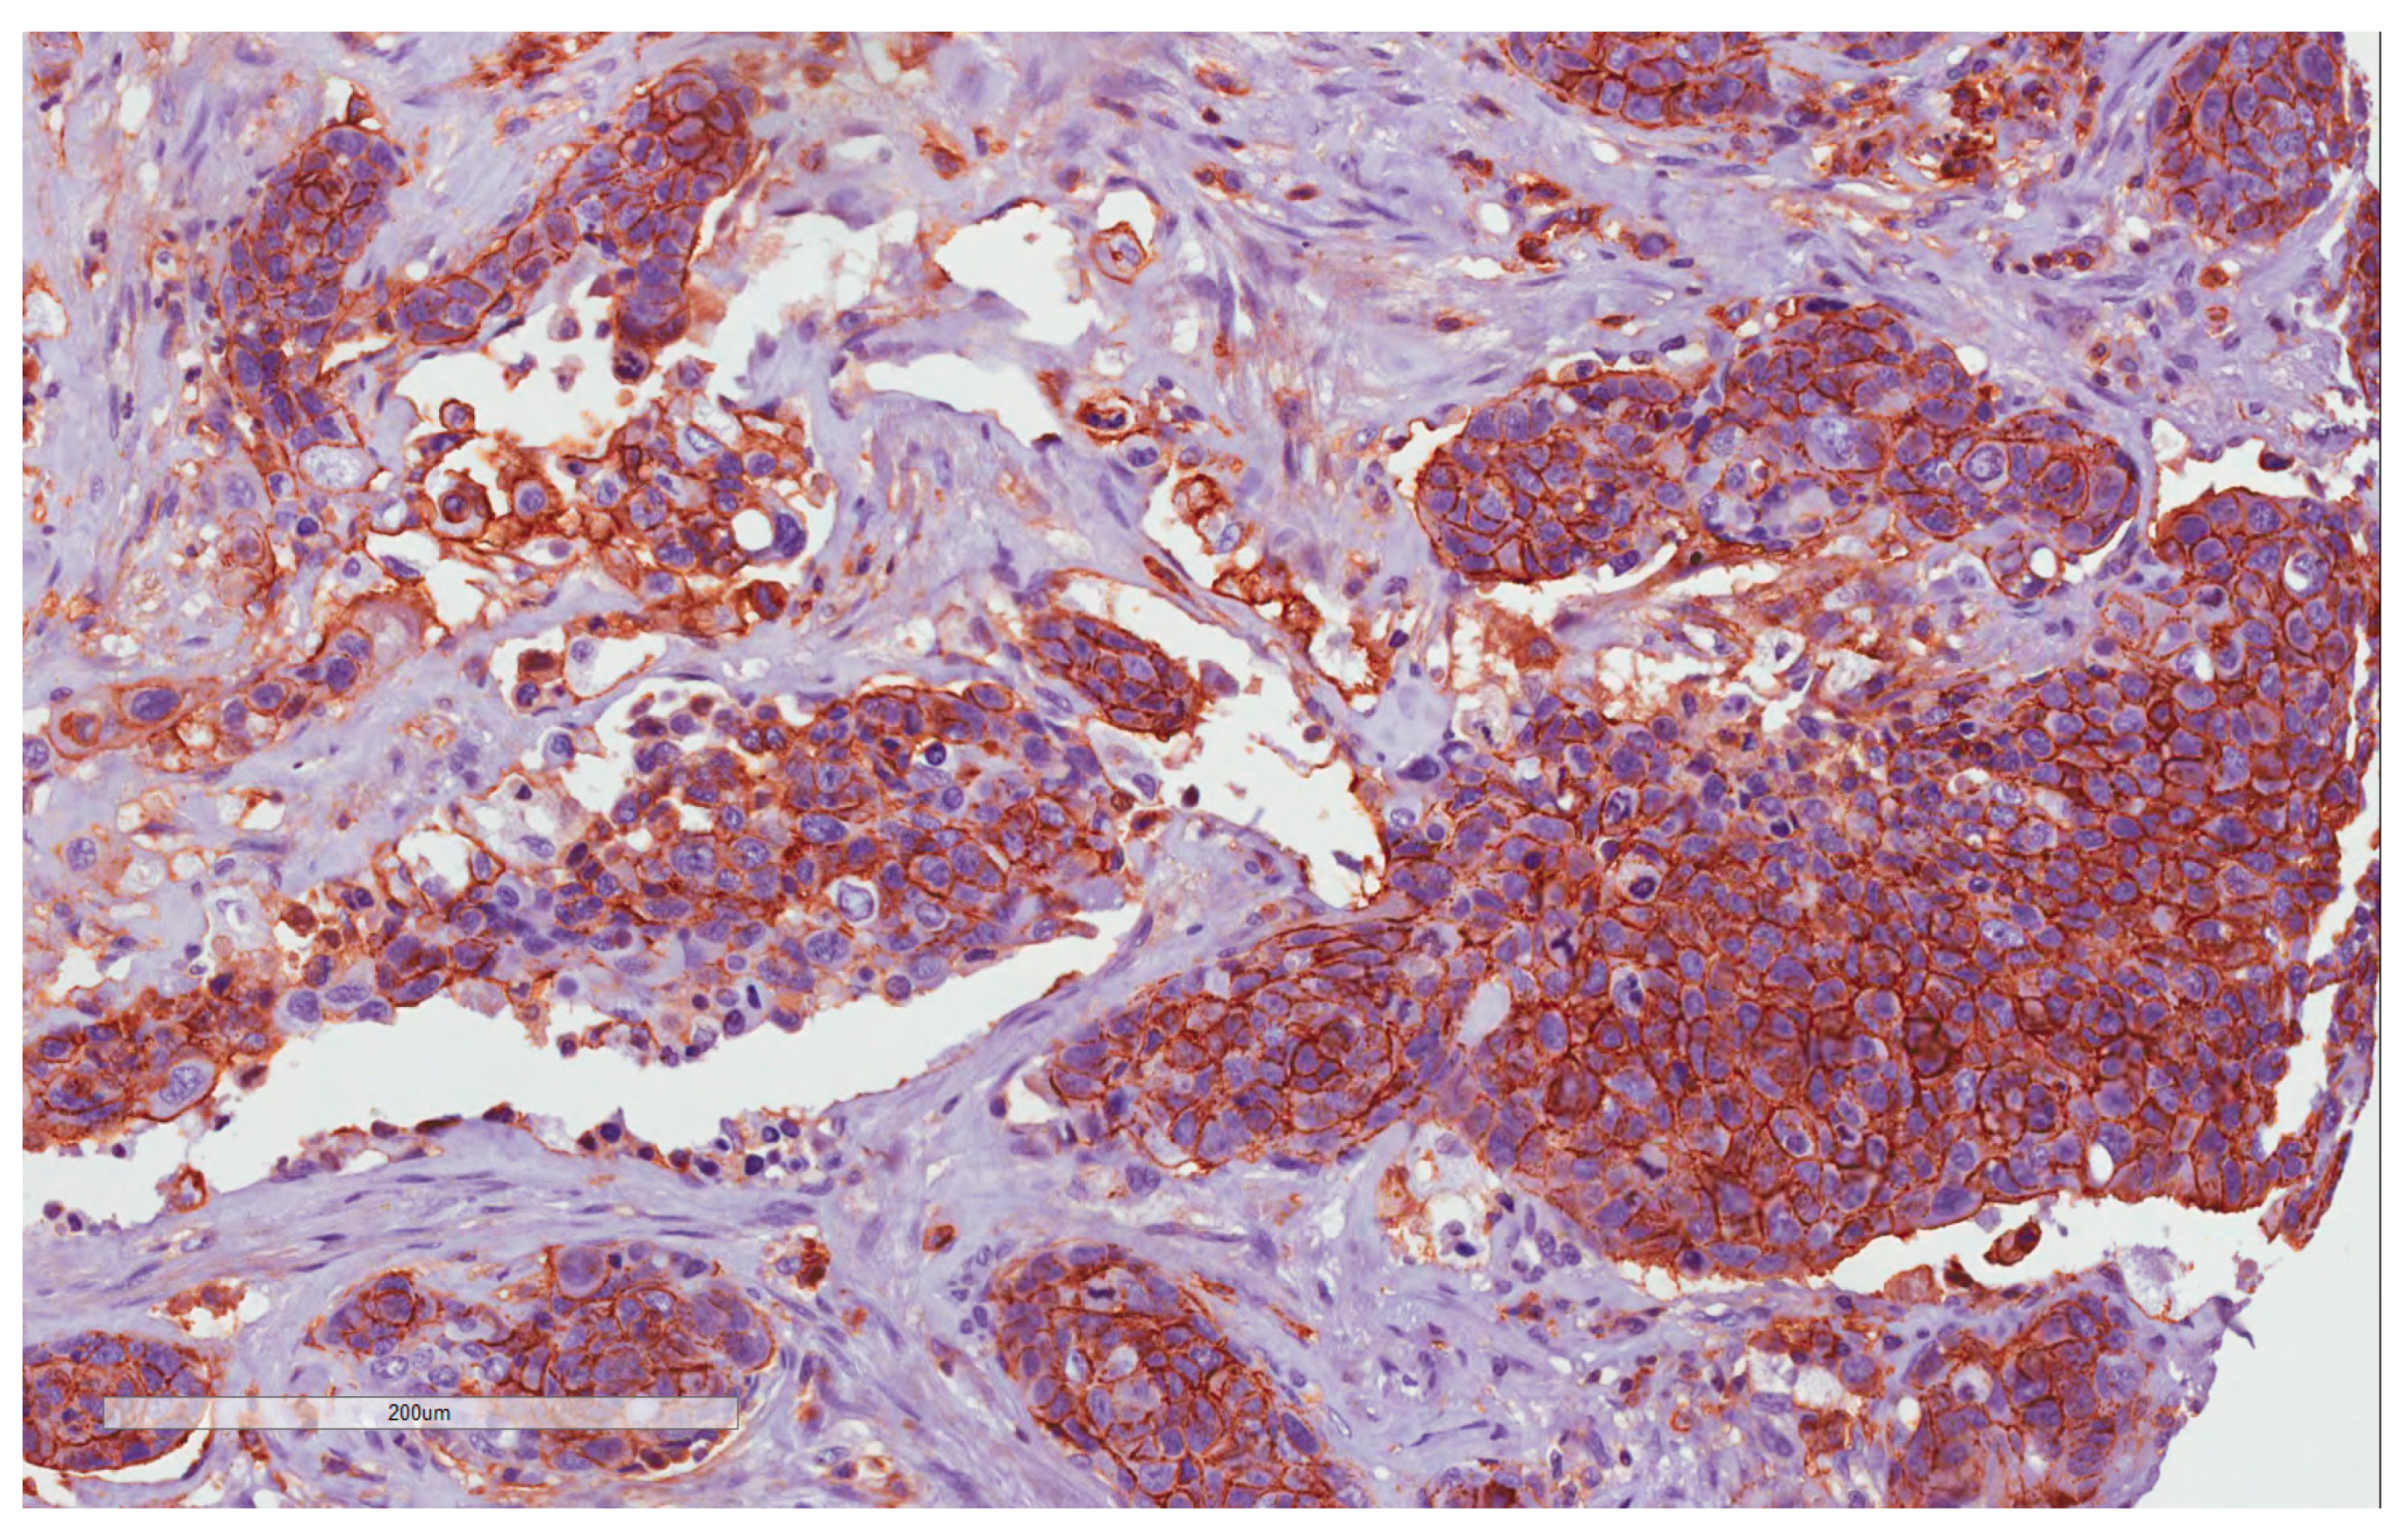

4.2. CD44 Expression